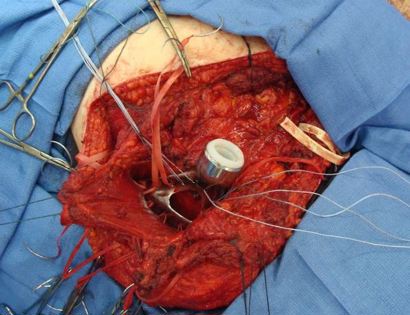

This image shows the scapula prosthesis inserted after the tumor, scapula, and margins have been removed.

In this image, ligaments are reconstructed with a dacron tube (surgical tape) and heavy sutures.